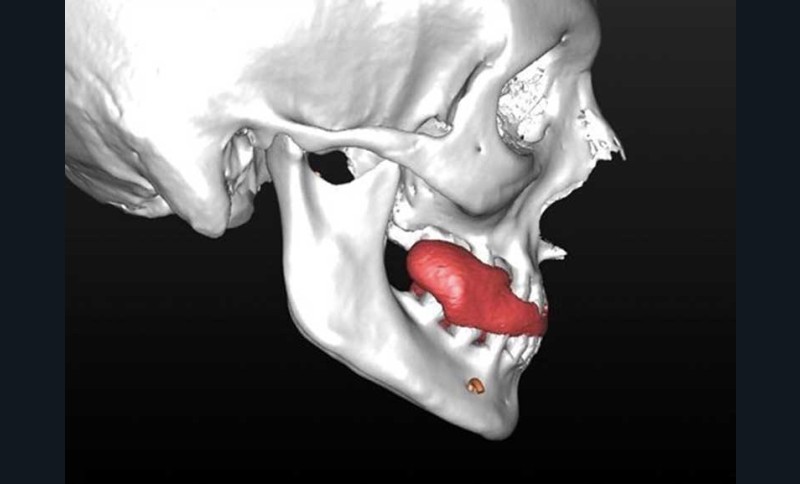

– élaboration des images 3D en isolant des différents constituants anatomiques : crâne et maxillaire, mandibule, dents, dispositifs d’orthodontie, implants endo-osseux et prothèses conjointes éventuelles, etc.

L’enregistrement des classiques modèles en plâtre (en occlusion corrigée de Classe 1) à l’aide d’un scanner conventionnel (format DICOM) ou par empreinte optique (format STL) est ensuite intégré au squelette dento-squelettique ; étape désignée « matching des modèles ».

Rendue possible par la visualisation 2D et 3D interactive des données du patient, elle constitue la première « phase clinique » du processus numérique (flux numérique). Le chirurgien peut aisément visualiser les rapports des bases squelettiques et l’occlusion pathologique, tandis que la sélection interactive de coupes natives (axiales) ou reconstituées (coronales, frontales, sagittales) favorise la compréhension de la…